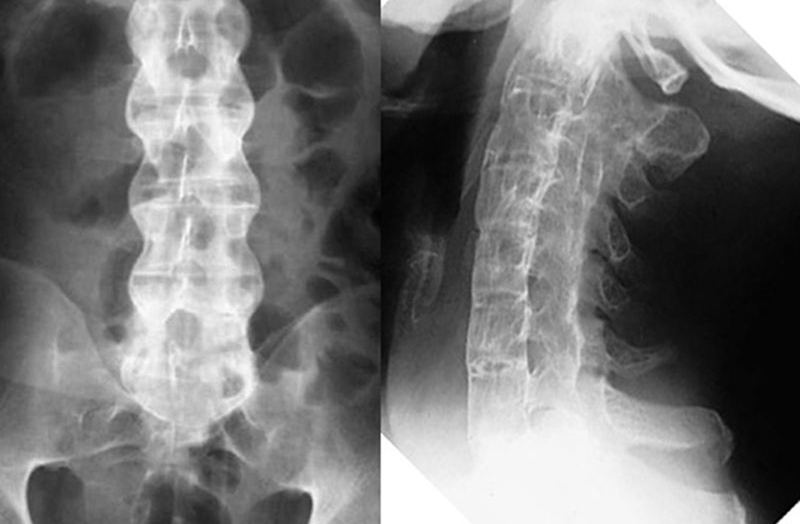

Thoái hóa cột sống: Thoái hóa cột sống dính khớp2

Thoái hóa cột sống dính khớp gây tình trạng viêm cột sống dính khớp

• Thoái hóa cột sống dính khớp: Đây là tình trạng viêm cột sống dính khớp mãn tính kéo dài, đau và tổn thương sẽ xuất hiện ở vùng xương chậu, cột sống và các khớp chi dưới. Một số đốt sống sẽ bị dính lại với nhau gây sưng dẫn đến tình trạng khó cử động, có thể gù, vẹo, thậm chí tàn phế.